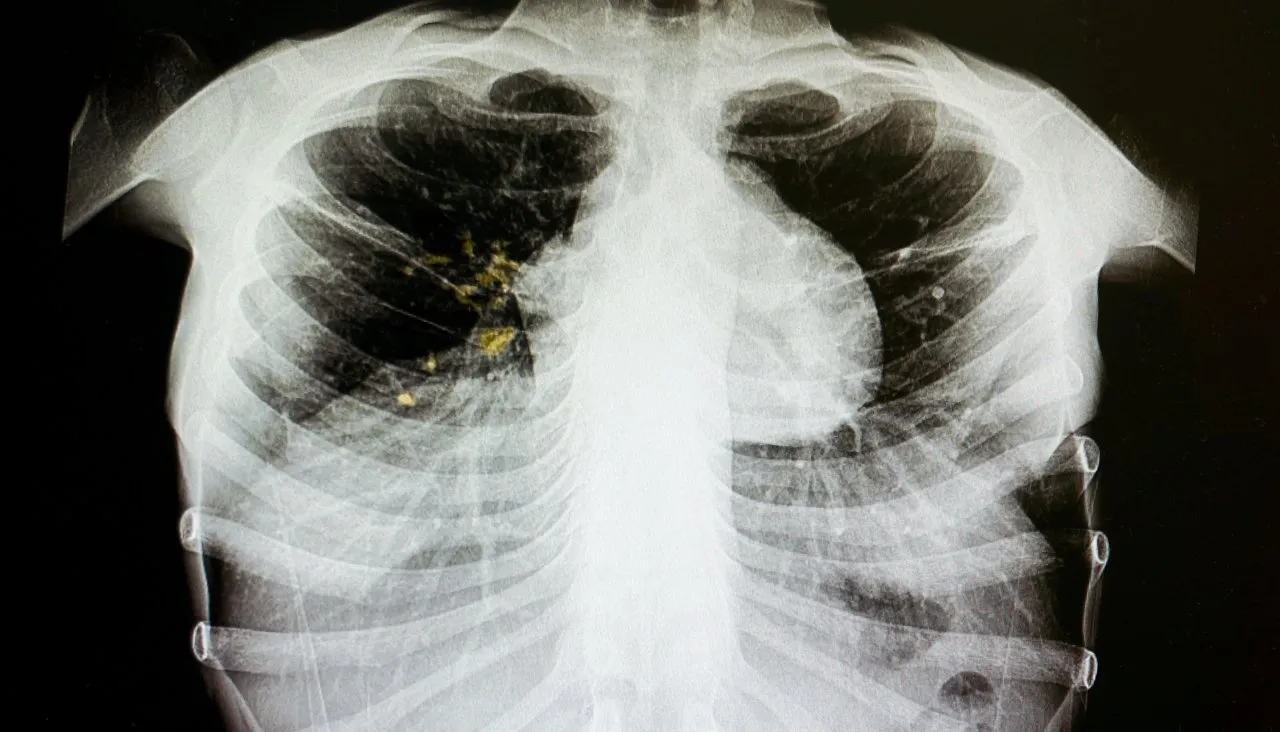

Как понять, что у меня туберкулез? От кашляющего соседа в автобусе можно заразиться? Задайте свой вопрос про туберкулез — а мы ответим